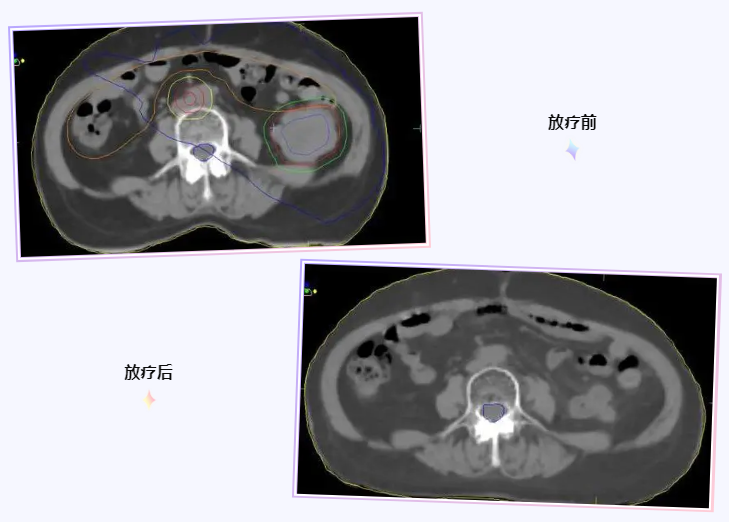

9月14号给患者做了放疗前的定位,从定位CT上可以清楚的知道病灶的大小和位置情况,周围都有什么重要的器官需要保护,预判在治疗过程中以及治疗结束之后可能会出现哪些不良反应。这个患者左中腹病灶比较大,大小约5.3cm*6.2cm,与左肾下极和一段小肠关系密切,制定放疗计划时严格保护左侧肾脏和临近肠管。

第二天放疗计划完成,开始放疗,至10月26号放疗完成28次,肿瘤中心剂量达到56Gy,临近肿瘤的肠管此时受量大约为50 Gy,过程中没有出现明显不适。此时夏主任让复查一个腹部CT,看看病灶及周围组织情况,结果惊喜的发现,左中腹那个6公分大的病灶消失了。把这个好消息告诉患者和家属,他们都很兴奋,连连表示感谢,夏主任嘱咐患者和家属,现在放疗结束了,先回家休息,2-3个月以后回来复查,期间有任何不舒服的症状都要及时跟我们联系。